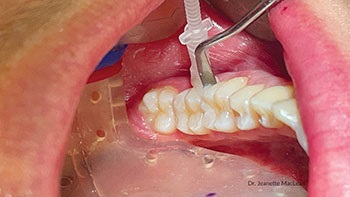

Patient 2: Proximal use

Curadont Cases

Fig. 5: A 19-year-old male with incipient proximal caries lesion on the distal of the mandibular left first permanent molar.

Fig. 6: Curodont was applied to the proximal contact using a plastic instrument to help push the liquid out of the sponge into the embrasure space.

Fig. 7: A six-month follow-up bitewing shows the distal lesion on the mandibular left first permanent molar has not cavitated.